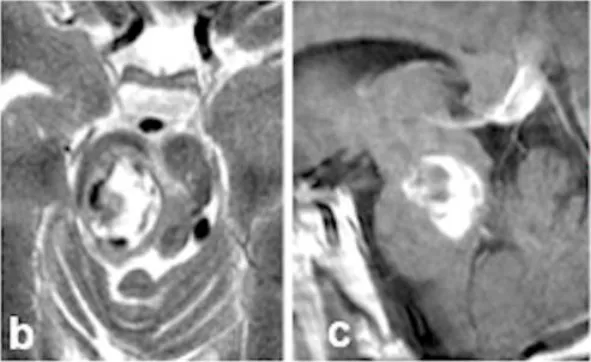

这次出血带来了严重后果。新发出血导致他出现左侧肢体轻偏瘫和感觉减退,右侧外展神经及面神经麻痹,更伴随意识水平下降。术前MRI清晰显示一个22mm的出血性病灶(图b-c)向尾侧延伸(图c),将患者推向生命危急关头。

术后影像(图f-g)和术中记录共同证实,病灶已实现全切,出血得到彻底控制。